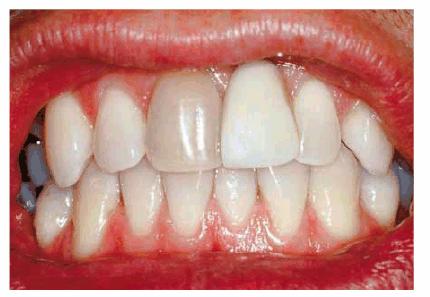

INTRINSIC STAINS

Much of the etiology of internal stains has been discussed in the first volume

of this textbook. Typically, bleaching with 10% carbamide peroxide in a

custom-fitted tray easily treats discolorations due to aging, smoking, or

chromogenic foods, and beverages (Figures 16-16A 16-16B 16-17A, and 16-17B). Although these types of stains

generally require only 2 to 6 weeks of bleaching treatment, some are more

stubborn. Nicotine staining of long-term duration may require as long as 3

months of nightly treatment (Figures 16-18A, and 16-18B).48 Tetracycline

staining may take anywhere from 2 to 12 months of nightly treatment.49

Figure 16-16A: Some teeth darken over time from chromagenic foods. Some patients' teeth are just naturally yellow.

Figure 16-16B: Whitening of the maxillary teeth using 10% carbamide peroxide in a custom tray results in a more pleasing smile. This patient is now interested in closing the spaces.

Figure 16-17A: Some teeth darken through natural aging.

Figure 16-17B: Whitening of the maxillary teeth using 10% carbamide peroxide in a custom tray produces a normal progression of color from gingival to incisal edge but offers a more pleasing, younger look to the patient.